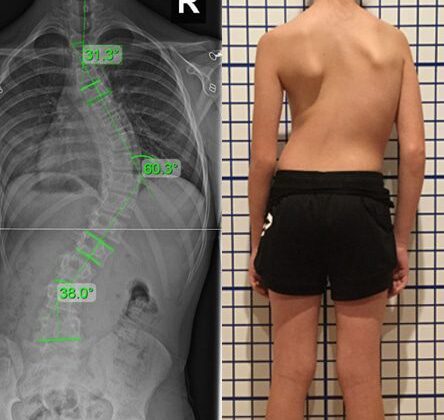

3. درجة الانحناء الحالية

بشكل عام:

- أقل من 20 درجة → خطر أقل

- 20 إلى 30 درجة → خطر متوسط

- أكثر من 30 درجة → خطر أعلى للتطور

👉 لذلك، كلما زادت الدرجة، زادت الحاجة للمتابعة الدقيقة.

هل يمكن أن تزيد درجة اعوجاج العمود الفقري البسيط عند طفلك؟

لفهم الموضوع بشكل أدق، يجب تعريف “تطور الحالة”:

👉 أي زيادة في درجة الانحناء مع الوقت

ولكن علميًا:

- إذا كانت الدرجة أقل من 20

👉 يُعتبر التطور زيادة 10 درجات أو أكثر - وإذا كانت بين 20 و30

👉 يُعتبر التطور زيادة 5 درجات أو أكثر

👉 لذلك، حتى الزيادة البسيطة قد تكون مهمة.